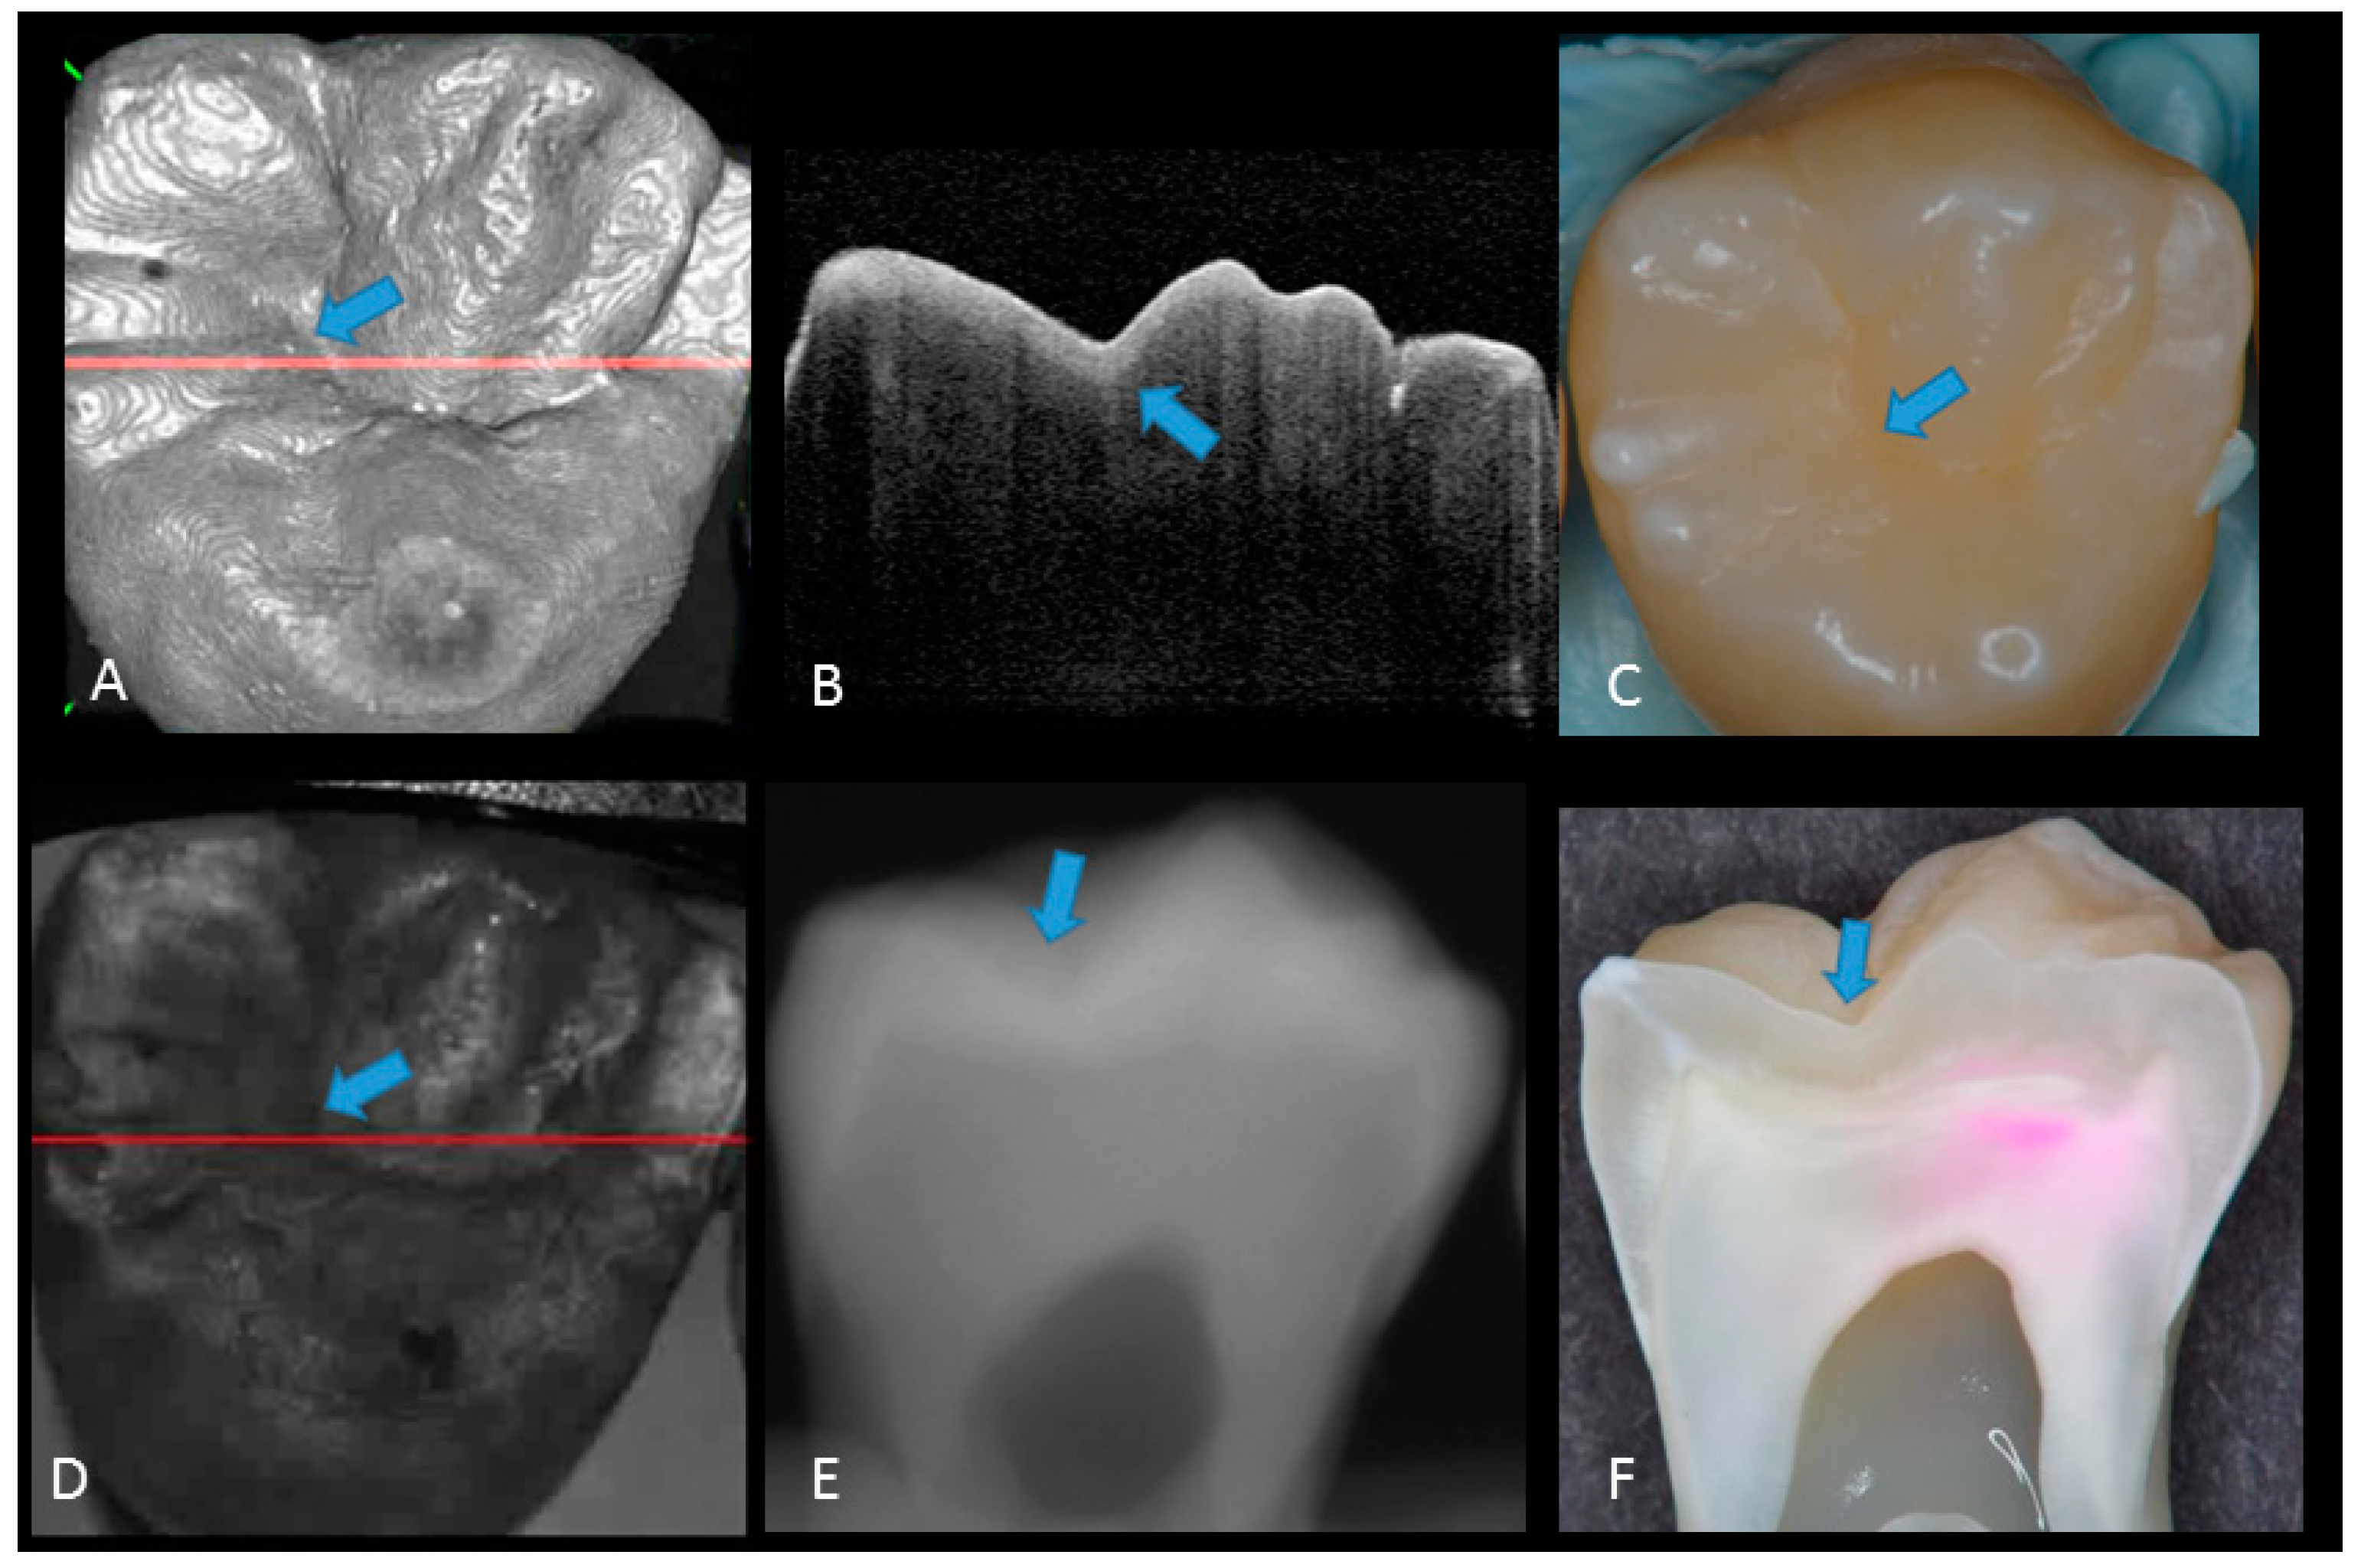

2. Materials and Methods

2.1. Specimen Preparation

2.2. Photography and X-ray Imaging

2.3. Optical Coherence Tomography

2.5. Validation of the Actual Scores